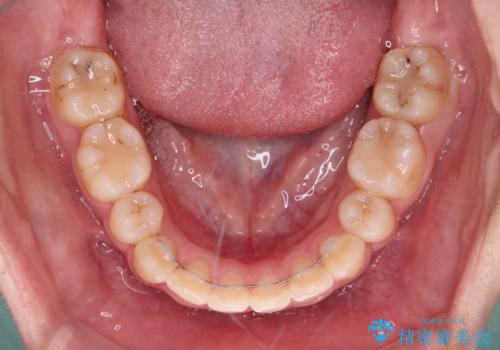

正中位置の改善に時間がかかることが予想され、2年半を治療期間の目標としておりましたが、20歳と年齢が若いこともあり、2年2ヶ月で治療を終えることができました。